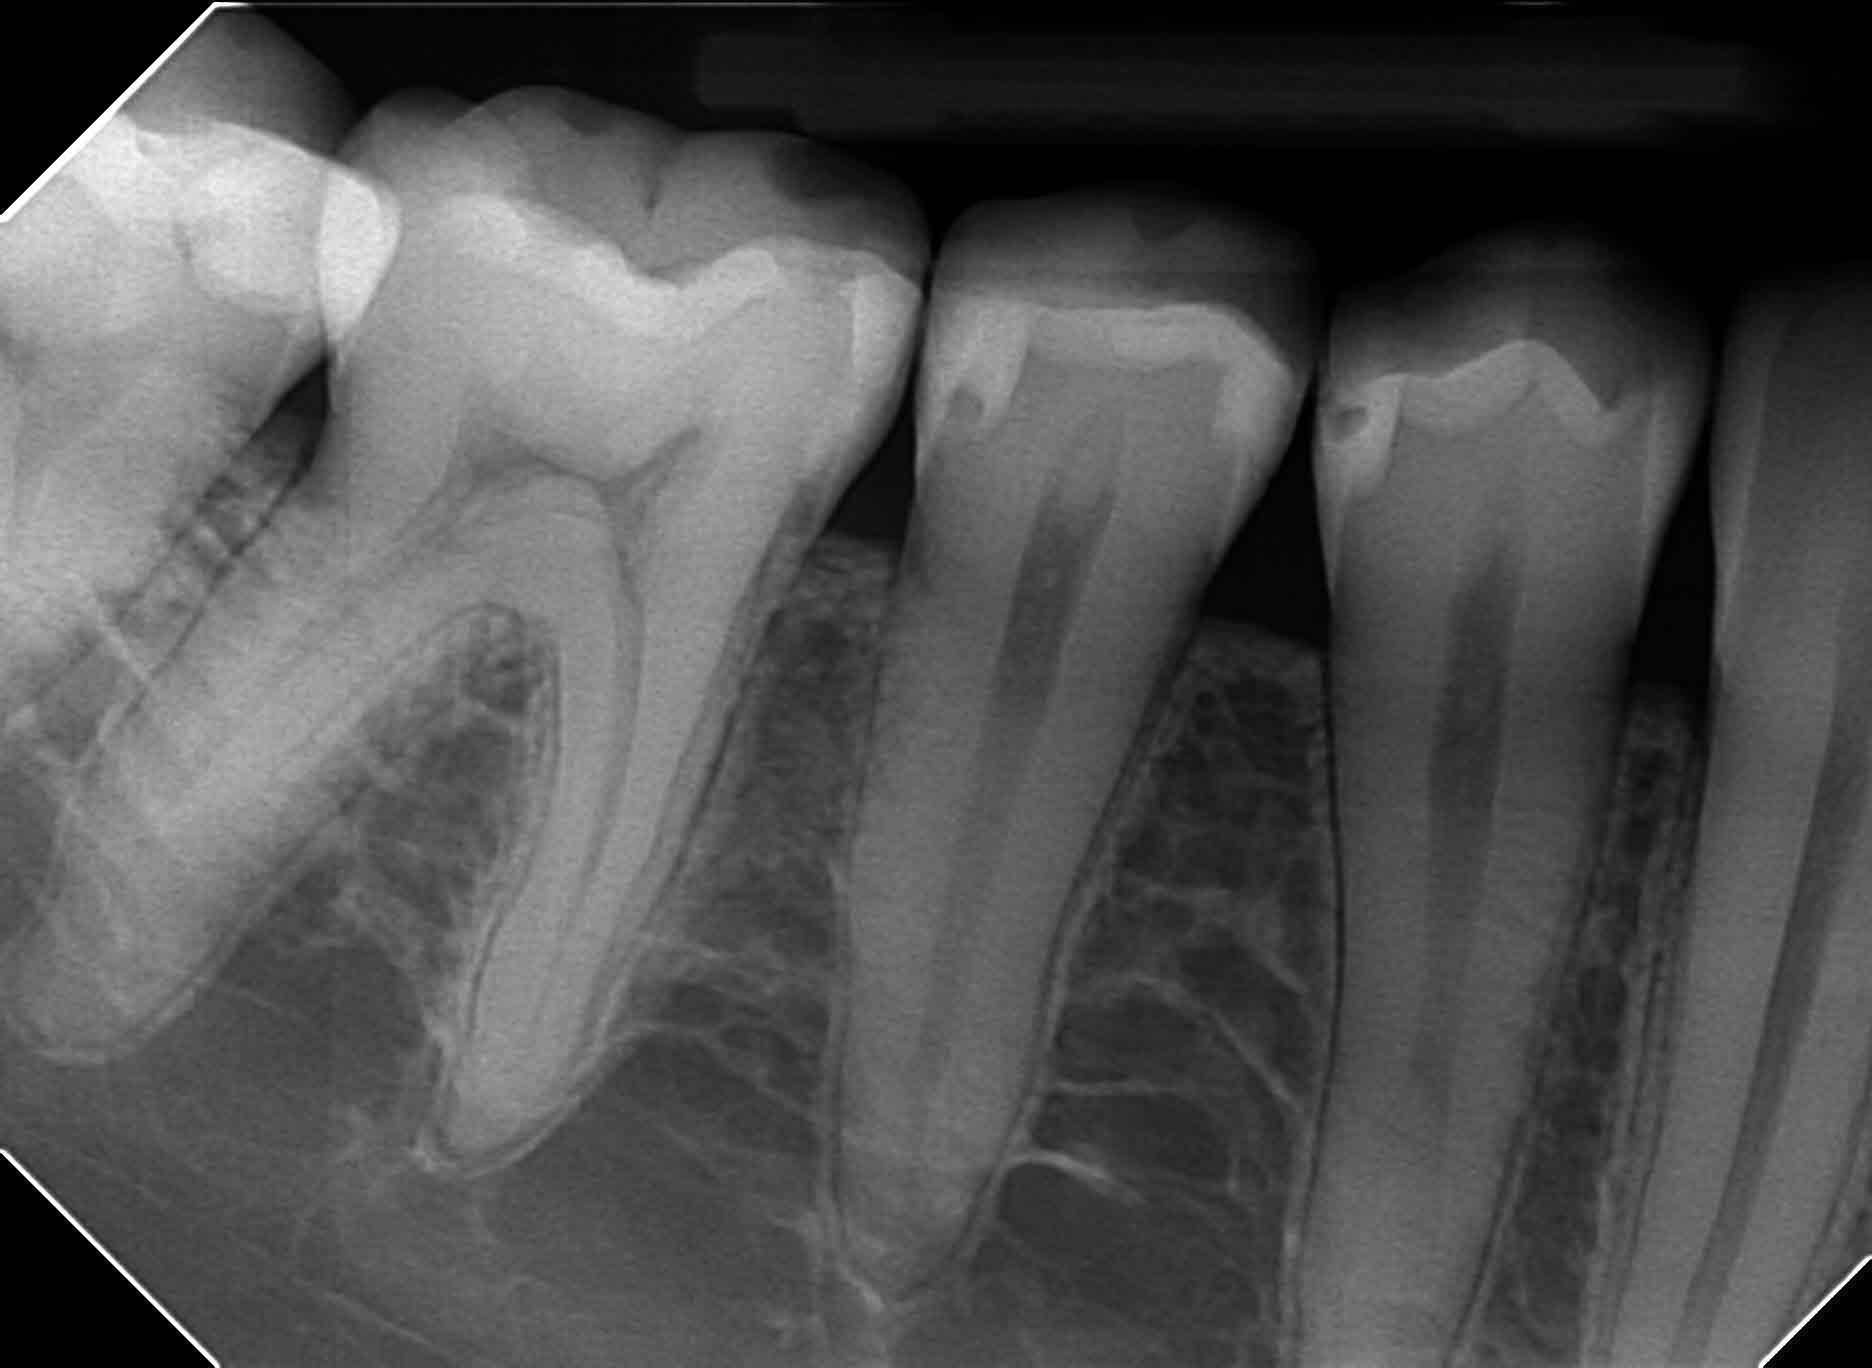

Abban az esetben, mikor csak egy vagy két fogat szükséges vizsgálni, akkor úgynevezett szájüregi felvétel, kisfelvétel készül. Ezek a felvételek digitális módon készülnek, ennek következtében a pácienst nagyon minimális sugárterhelés éri.

Az intraorális felvétel jóval részletgazdagabb, mint a panoráma felvétel. Ilyen röntgen kép készül a gyökérkezelések előtt, közben és a gyökértömés ellenőrzésekor. Tömések széli záródását, és az apró a fog oldalsó részén elhelyezkedő szuvasodást is ki tudja mutatni.